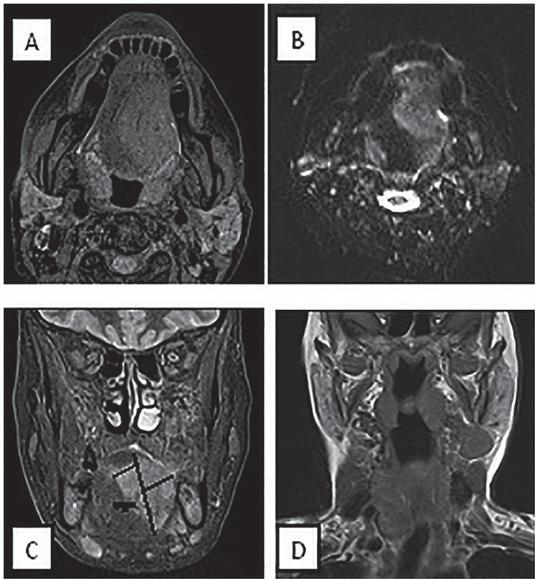

MRI of a 75-years-old female with sizable tongue mass crossing the midline (T4N1 disease). (A) Axial T1 post contrast fat suppression (B) Axial DWI (C) Coronal T1 post contrast fat suppression (D) Coronal T1 post contrast shows metastatic cervical lymph nodes. Tumour thickness is the sum of the two horizontal black lines drawn perpendicular to the vertical black line connecting maximum tumour junction distance and was determined as 30 mm. The thick black line representing para-lingual distance between the tumour and the para-lingual space was determined as – 10 as the tumour margin extends beyond the midline by 10 mm